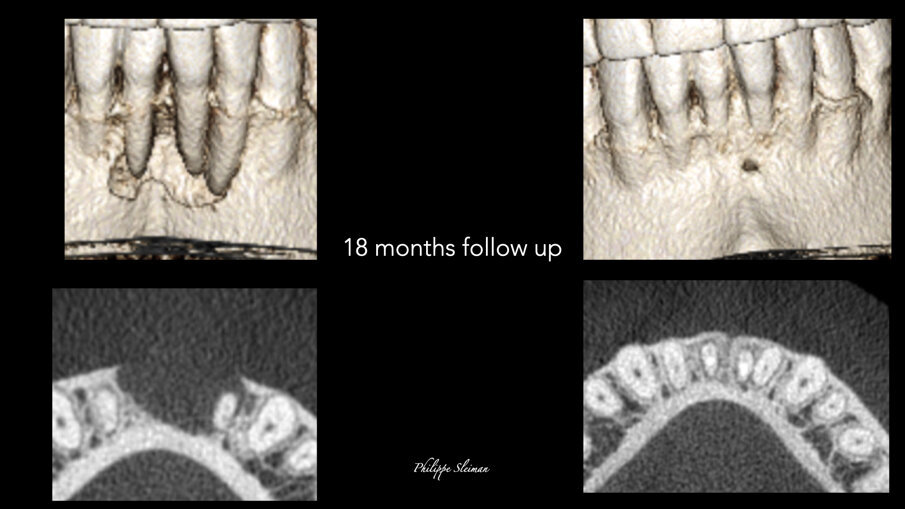

Slike 7a–e: Poređenje horizontalnih prikaza i-CAT skeniranja snimljenih pre operacije (a i b) i tokom devetomesečnog praćenja (c) i 18-mesečnog praćenja (d i e), koji pokazuje potpuno zarastanje područja

Slike 8a–d: Poređenje kostiju i horizontalnih prikaza preoperativnog (a i b) i 18-mesečnog praćenja i-CAT skeniranja (c & d) u vezi sa zarastanjem kosti i zatvaranjem džepa

Poređenje i-CAT skenova napravljenih pre operacije i nakon devetomesečnog i 18-mesečnog praćenja pokazalo je potpuna regeneracija kortikalne i trabekularne kosti sa velikim biološkim detaljima, pokazujući čak i frenum (slike 7 i 8). Preoperativni prikaz kosti jasno je pokazao preoperativni veliki horizontalni i vertikalni defekt kosti i otvoreni parodontalni defekt, a sada se na tom mestu može videti lepo regenerisana kost prirodnog izgleda i nastanak mandibularnog nerva. Na sreću, kost je nastavila da raste vertikalno (slika 9).